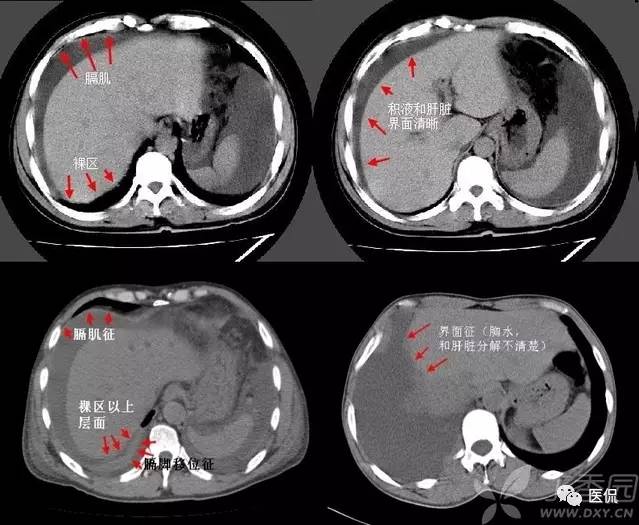

胸膜下弧线(SCLC)

肺胸膜下弧线影像(SCLS)的病理基础

国外学者对此征象的CT与病理对照研究指出,SCLS是细支气管周围纤维性增厚及肺纤维化引起的肺泡变扁和肺不张。构成SCLS的肺不张为肺脏皮质与髓质交界处的盘状肺不张,肺不张的发生与肺间质纤维化后肺脏的顺应性减低有关。指出肺脏蜂窝状改变的边缘融合也可形成SCLS,SCLS位于蜂窝之间,这在HRCT图像上可清楚地显示。临床发现,SCLS发生在慢性肺炎之后,少数发生在慢性支气管炎合并肺间质纤维化患者吸气不足状态,深吸气时大部分消失,也有发生在阻塞性肺不张后,这些表明SCLS为肺脏局部通气不良发生的盘状肺不张。胸膜广泛钙化,SCLS与胸膜钙化的范围一致,肺内也有轻度的肺间质纤维化改变,胸膜钙化可能使胸膜下肺组织的顺应性下降,从而对SCLS的形成有促进作用。胸膜增厚与胸膜结节也可能引起类似的结果。

SCLS的HRCT形态特点

SCLS与生理性的肺下垂部线性影像不同,生理性胸膜下线位于肺脏的最低部,在仰卧位时位于下叶后部,而转变为俯卧位时下叶后部的线性影像消失,生理性胸膜下线多距胸膜下5mm以内,可合并局限性肺脏密度增高。而SCLS虽然在肺脏后部多见,但多超过一个肺段的范围,并可位于肺脏非下垂的部位。体位变换时其形态无变化,也不会消失。多数SCLS表面光滑、呈连续状,少数为不规则及不连续状。煤工尘肺的SCLS可有结节状影,或厚度较大。

SCLS的诊断意义

SCLS可见于多种肺间质纤维化的疾病,如慢性支气管炎合并肺间质纤维化,煤工尘肺,特发性肺间质纤维化,胶原病引起的肺间质纤维化,及结节病引起的肺改变等。慢性支气管炎,特发性肺间质纤维化,煤工尘肺及胶原病引起的肺脏改变等均可出现,占90.3%。以往一些作者曾认为SCLS在石棉肺多见,或认为此征象是石棉肺病人的特有表现。但临床研究的结果表明,SCLS是肺间质纤维化的一种常见征象,见于多种疾病。此外,SCLS还见于炎症、肺瘀血和吸气不足状态。对于肺间质纤维化的病例,SCLS为肺间质纤维化的早期改变。

SCLS周围无肺间质纤维化征象者占25.71%,仅有小叶内间质增厚及小叶间隔增厚者占28.57%,发生较多蜂窝改变的仅占20%。SCLS的长度与肺间质纤维化的严重程度有关,有人对随访的肺间质纤维化逐渐加重的患者,发现SCLS也由短线型发展为长线型。即使SCLS可发生在有蜂窝的部位,但蜂窝改变多较轻微,而在蜂窝改变较密集之处未能见到SCLS。有研究指出,SCLS开始发生在肺间质纤维化轻微的部位,5年后该部位发生严重蜂窝改变,SCLS则不能显示。这表明SCLS的发生、延长与肺间质纤维化加重有关,但出现严重蜂窝后SCLS则不能显示。

总之,SCLS可以变小或消失,表明SCLS有些为可逆的改变。不同的疾病SCLS在形态上多无显著的差异。煤工尘肺SCLS可有细小结节,此结节与肺内结节的形态相似,代表了煤工尘肺的形态特点。但对大多数疾病而言,SCLS缺乏鉴别诊断价值。